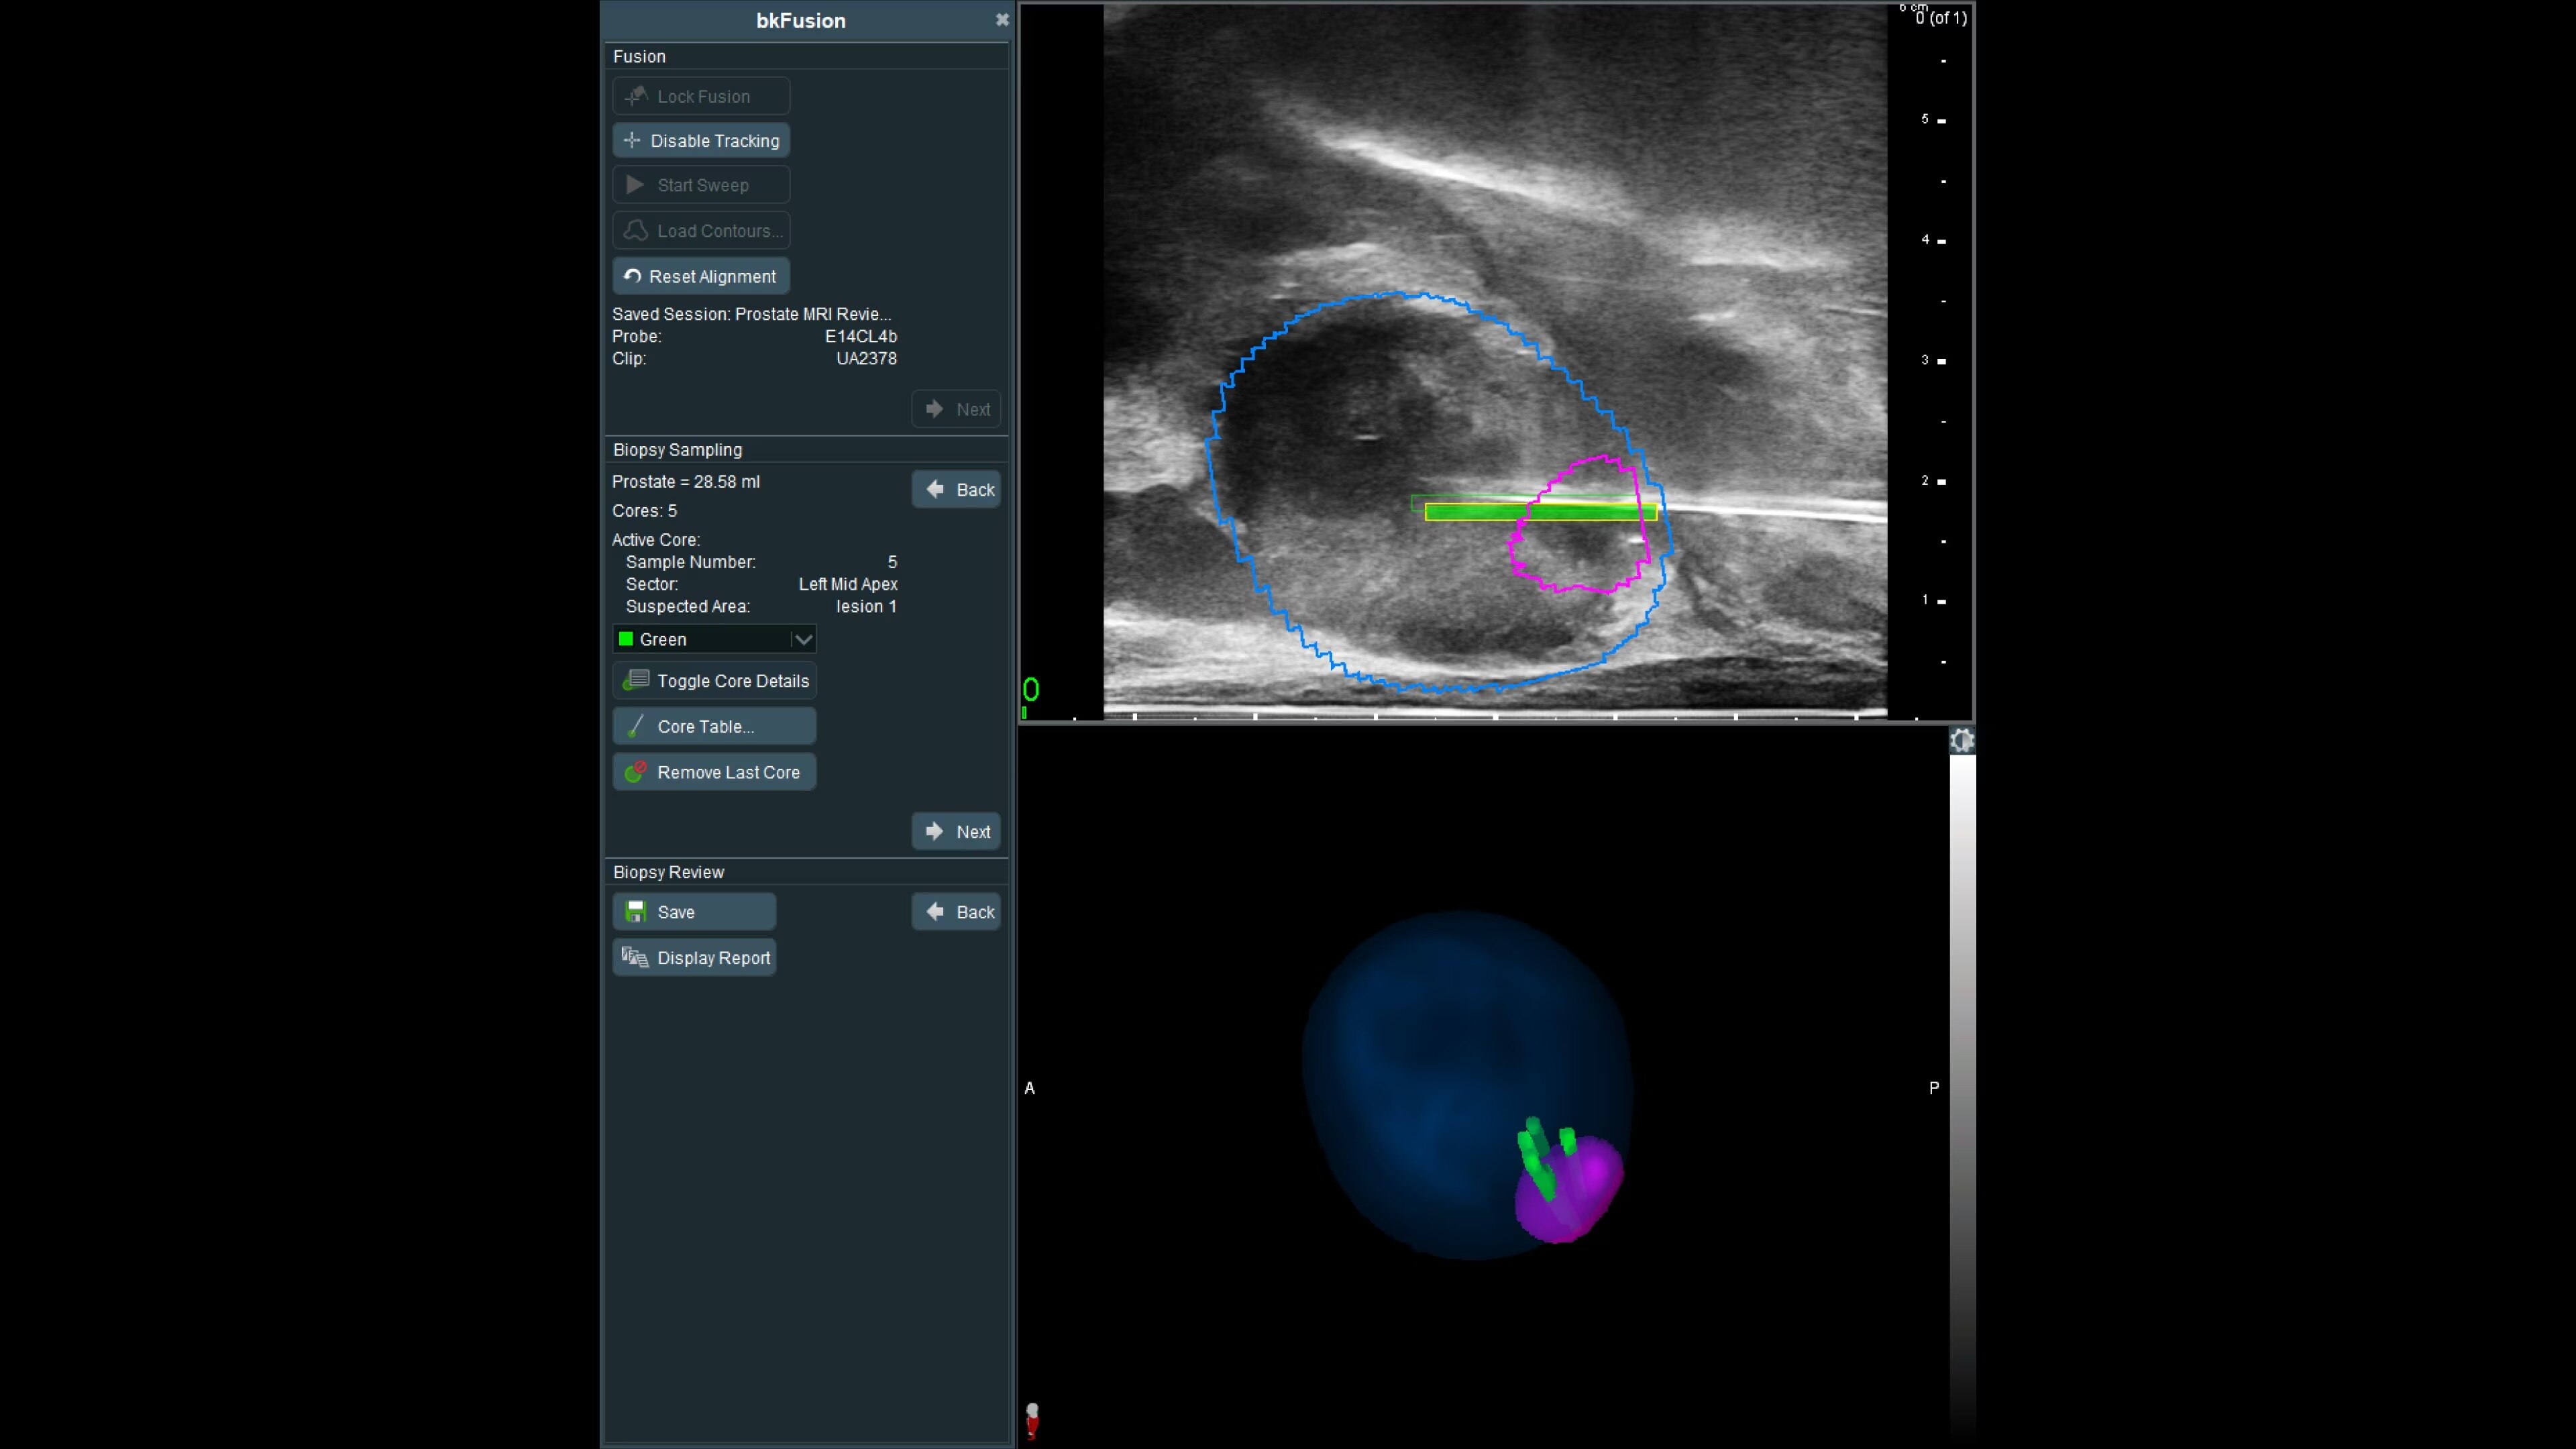

Effortless imaging with no calibration or 3D sweeps

bkFusion makes prostate biopsy imaging effortless with no additional steps or disruptions to the familiar biopsy workflow. No need to calibrate the system or perform 3D sweeps. Experience this easy guided workflow in the OR or clinic. Differences in patient positioning during MRI acquisition and biopsy can result in one in six lesions being reported in a different sector than they appear during US-guided biopsy.³ bkFusion's innovative Predictive Fusion® technology optimally reorients the supine MRI into LLD or lithotomy position, preventing registration errors before the procedure begins.

Enhance biopsy accuracy with Predictive Fusion®

Predictive Fusion® is the proprietary registration method allowing you to imediately see any errors in the overly of MRI and ultrasound images before and during the procedure. Utilizing rigid 2D slice registration, it eliminates distortion in merging 3D shapes, ensuring precise MRI-ultrasound fusion. If changes are needed, make simple, one-touch, micro-adjustments to updte the registration without calibration steps or 3D sweeps. Enhance your prostate biopsy accuracy with this advanced technology.